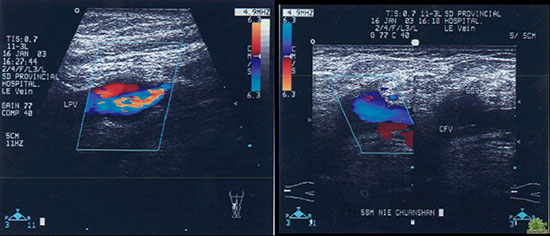

8.jpg

B超引导下穿刺